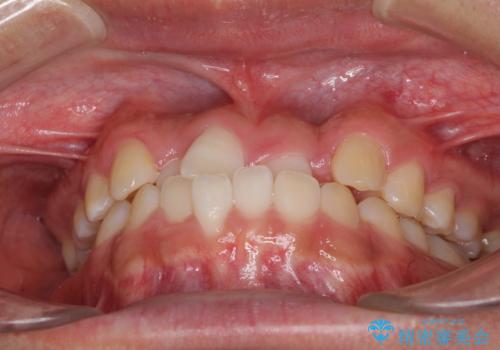

- 前歯のクロスバイトを気にして来院された患者様です。

美容専門の歯科医院を受診したところ、セラミックでの改善は無理と断られてしまったとのことでした。

歯がすり減って不揃いの形態となっていますが、まずは矯正治療によりクロスバイトを改善することとしました。